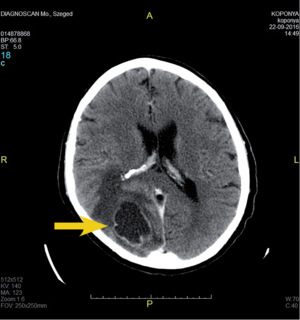

- CT: natív és kontrasztos – akut eset, staging, mész kimutatására.